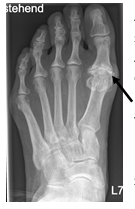

Fehlstellungen der 5. Zehe

Wenn an der 5. Zehe eine Krallenzehfehlstellung operiert wird, ist eine restliche Beweglichkeit im Mittelgelenk wichtig, damit es beim Tragen von Schuhen nicht zu Schmerzen kommt. Hier wird eine sog. Hohmann OP durchgeführt, bei der das Gelenk noch eine schmerzfreie Restbeweglichkeit hat. Eine andere Fehlstellung an der 5. Zeh ist der sog. Digitus quintus varus superductus, bei der der 5. Zeh nach oben und zur Seite steht. In der Regel ist hier die Verlängerung der Strecksehne und die Verlagerung eines Muskels notwendig, bei der auch ein Draht für vier Wochen eingebracht wird (sog. Lapidus Prozedur der 5. Zehe).

Im linken Bild ist der seitliche Hochstand der 5. Zeh deutlich zu erkennen. Im mittleren Bild ist schematisch die Verlagerung einer Sehne gezeigt, um die Fehlrotation zu korrigieren (Lapidus Prozedur). Im rechten Bild ist der Zeh nach der OP begradigt. Der zu erkennende Draht wird 4 Wochen nach der OP entfernt.